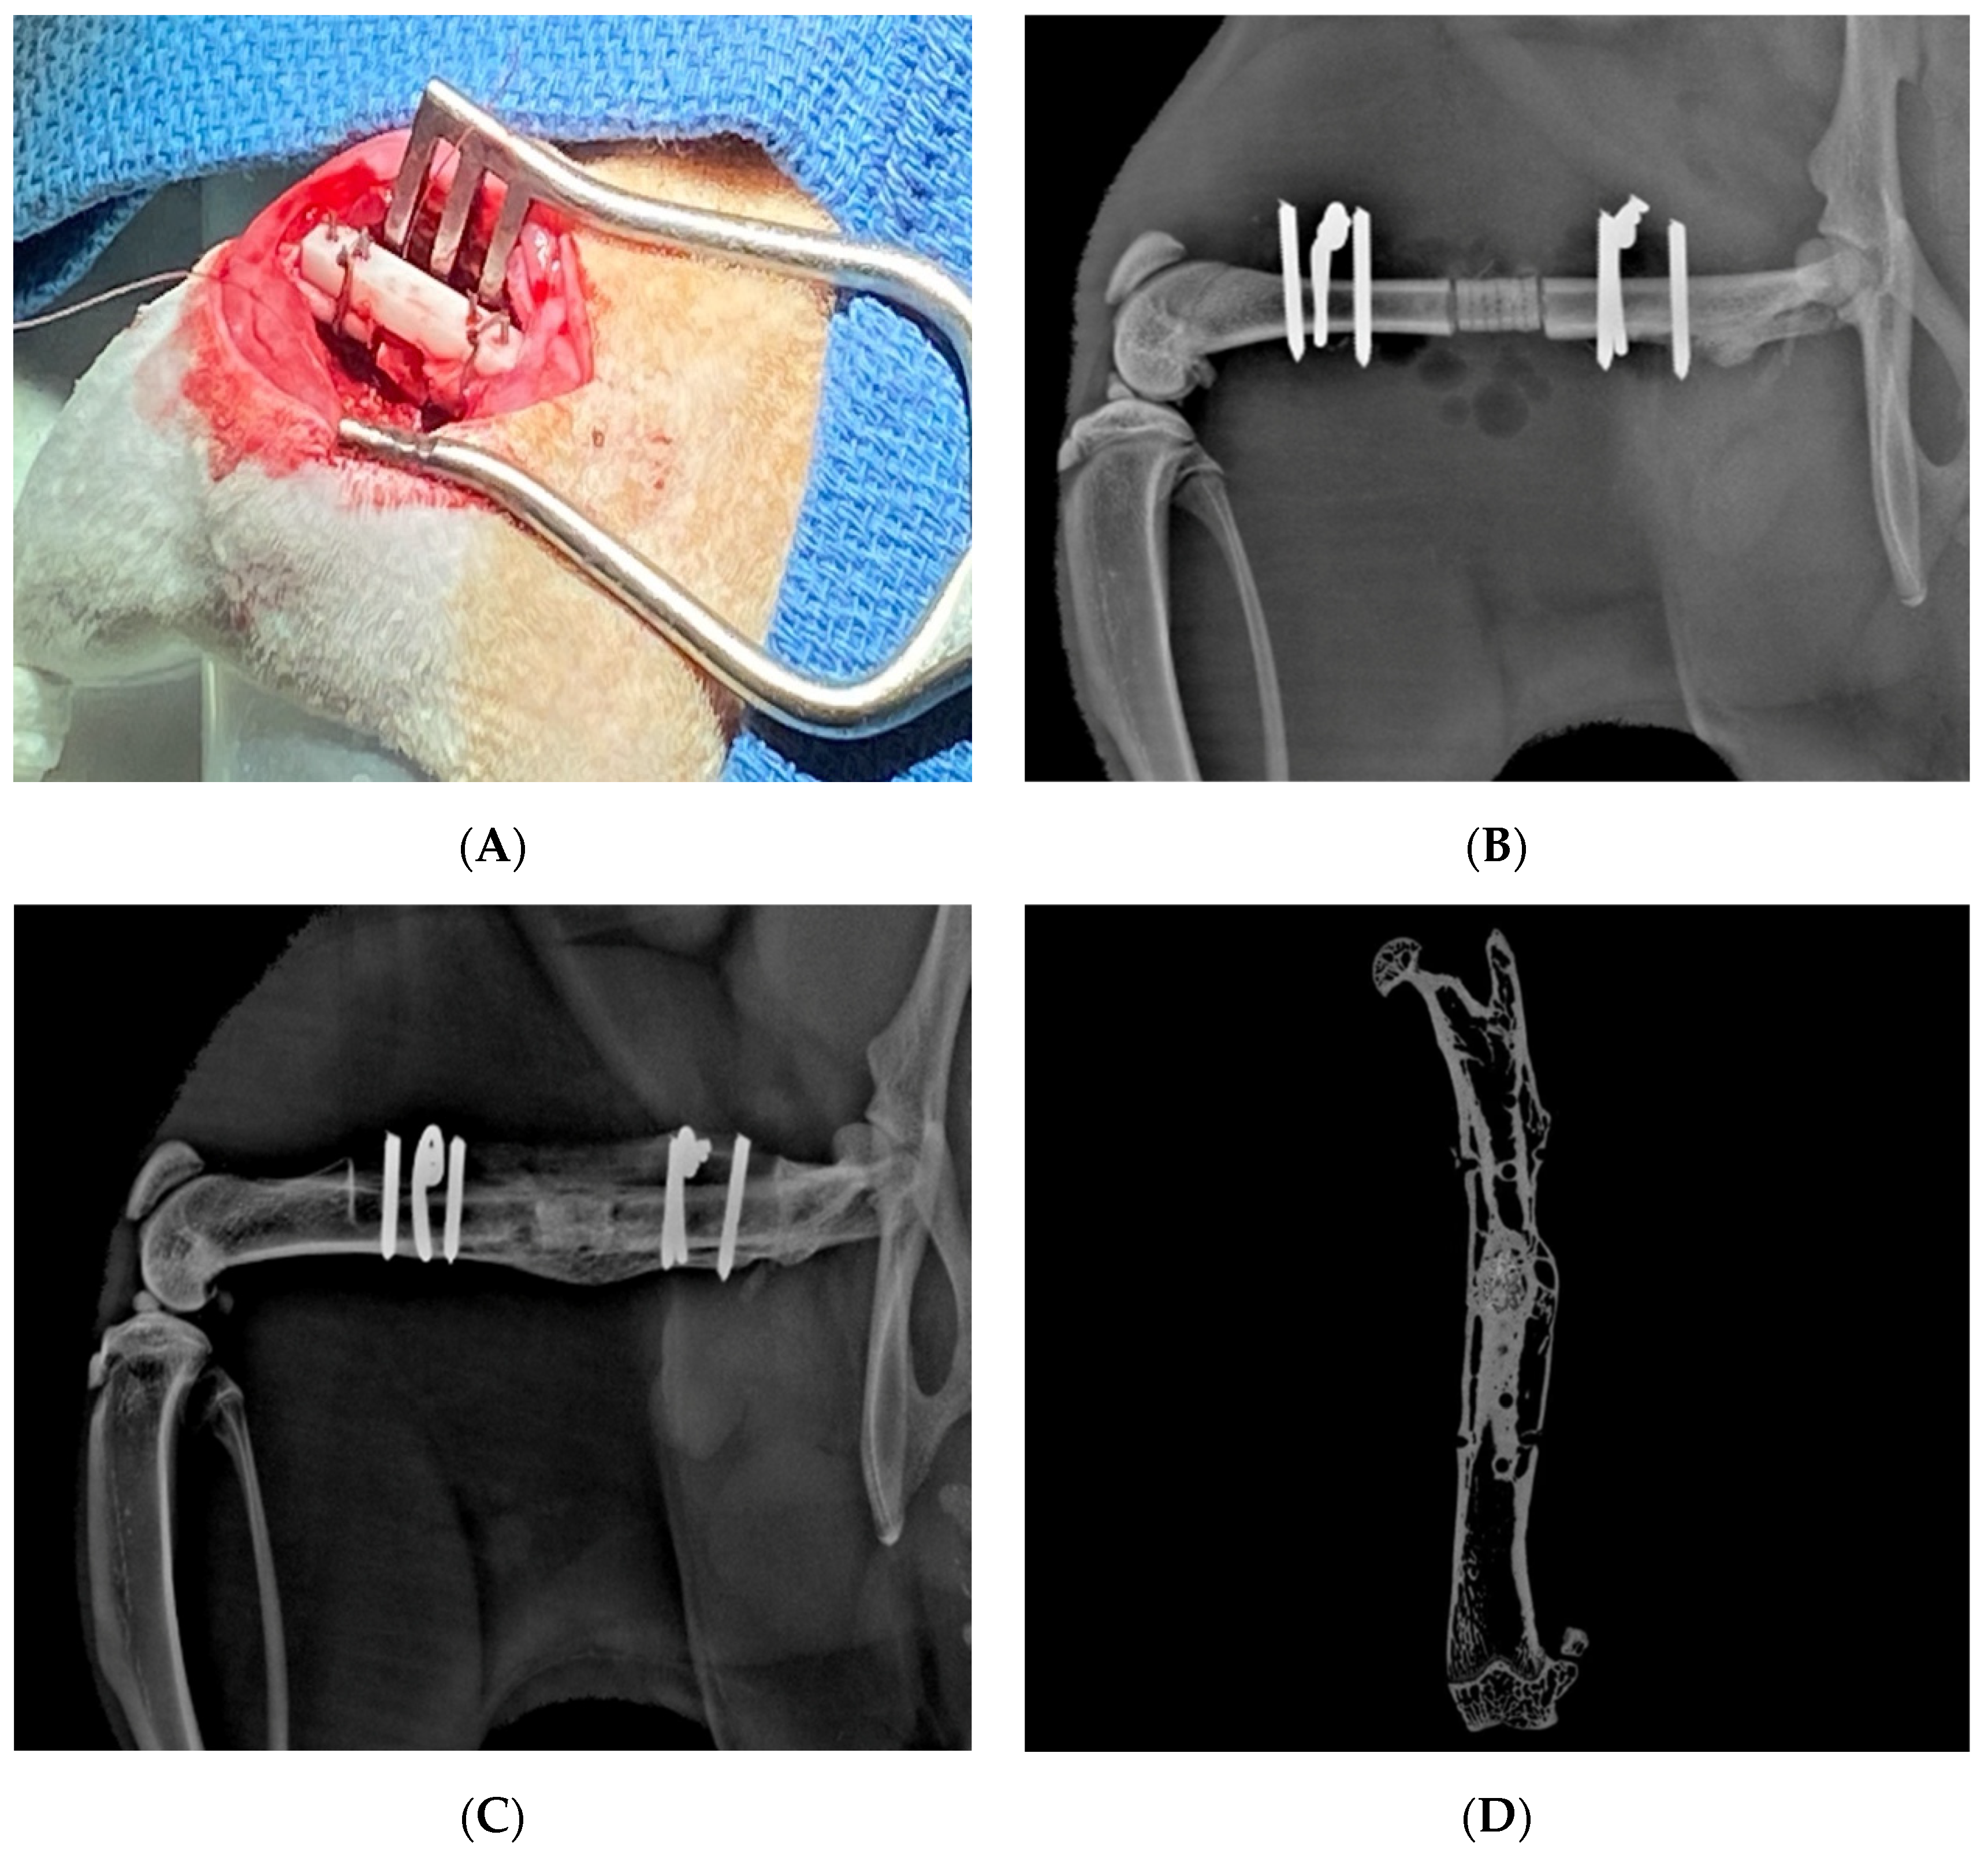

- Choi, S.; Oh, Y.I.; Park, K.H.; Lee, J.S.; Shim, J.H.; Kang, B.J. New clinical application of three-dimensional-printed polycaprolactone/β-tricalcium phosphate scaffold as an alternative to allograft bone for limb-sparing surgery in a dog with distal radial osteosarcoma. J. Vet. Med. Sci. 2019, 81, 434–439. [Google Scholar] [CrossRef] [Green Version]

- Franch, J.; Barba, A.; Rappe, K.; Maazouz, Y.; Ginebra, M.-P. Use of three-dimensionally printed β-tricalcium phosphate synthetic bone graft combined with recombinant human bone morphogenic protein-2 to treat a severe radial atrophic nonunion in a Yorkshire terrier. Vet. Surg. 2020, 49, 1626–1631. [Google Scholar] [CrossRef]